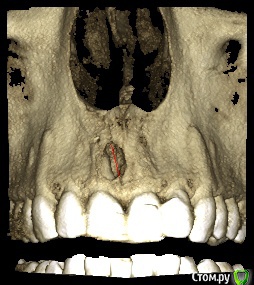

dentikl Опубликовано 22 декабря, 2016 Автор Поделиться Опубликовано 22 декабря, 2016 Потому что дефект 3-х стеночный и не выходит за границы контура челюсти,об'ем конечно кости уменьшаетсявот этот случай требует мембраны и индуктора?Ретроградно пломбировать даже если пройду на ревизии? Ссылка на комментарий

dentikl Опубликовано 22 декабря, 2016 Автор Поделиться Опубликовано 22 декабря, 2016 Зачем тогда вообще резекция!!!?там я фотки повесил.с Вашей точки зрения индуктор и мембрана нужны(Вы бы использовали в этом конкретном случае?) Ссылка на комментарий

Доктор Добрых Дел Опубликовано 22 декабря, 2016 Поделиться Опубликовано 22 декабря, 2016 В области 11 случайно не трещина корня? Медиально очаг деструкции как-то намекает на это 1 Ссылка на комментарий

Тимур86 Опубликовано 22 декабря, 2016 Поделиться Опубликовано 22 декабря, 2016 киста сбоку говорит о том что в корне скорее всего трещина Ссылка на комментарий

Bier Опубликовано 22 декабря, 2016 Поделиться Опубликовано 22 декабря, 2016 не трещина там, а латераль скорее всего. Так высоко корень только от удара может сломаться. dentikl методика РВК применяется только при невозможности или безуспешности ортоградного лечения. Т.е. в вашем случае оперировать не нужно, нужно ждать излечения. Если же вы проводите РВК - единственным смыслом этой операции является установка апикальной пломбы, желательно не короче 3-4мм вглубь канала. Прорут, Триоксидент, IRM, или биокерамика - подходят для этих целей. 4 Ссылка на комментарий

dentikl Опубликовано 3 января, 2017 Автор Поделиться Опубликовано 3 января, 2017 В области 11 случайно не трещина корня? Медиально очаг деструкции как-то намекает на этоВы правы.Там таки была перфа не середине мщ поверхности корня.Кисту извлекли,перф прикрыли,жду. Ссылка на комментарий

dentikl Опубликовано 3 января, 2017 Автор Поделиться Опубликовано 3 января, 2017 киста сбоку говорит о том что в корне скорее всего трещинаДа,там была перфа,Вы-правы. Ссылка на комментарий